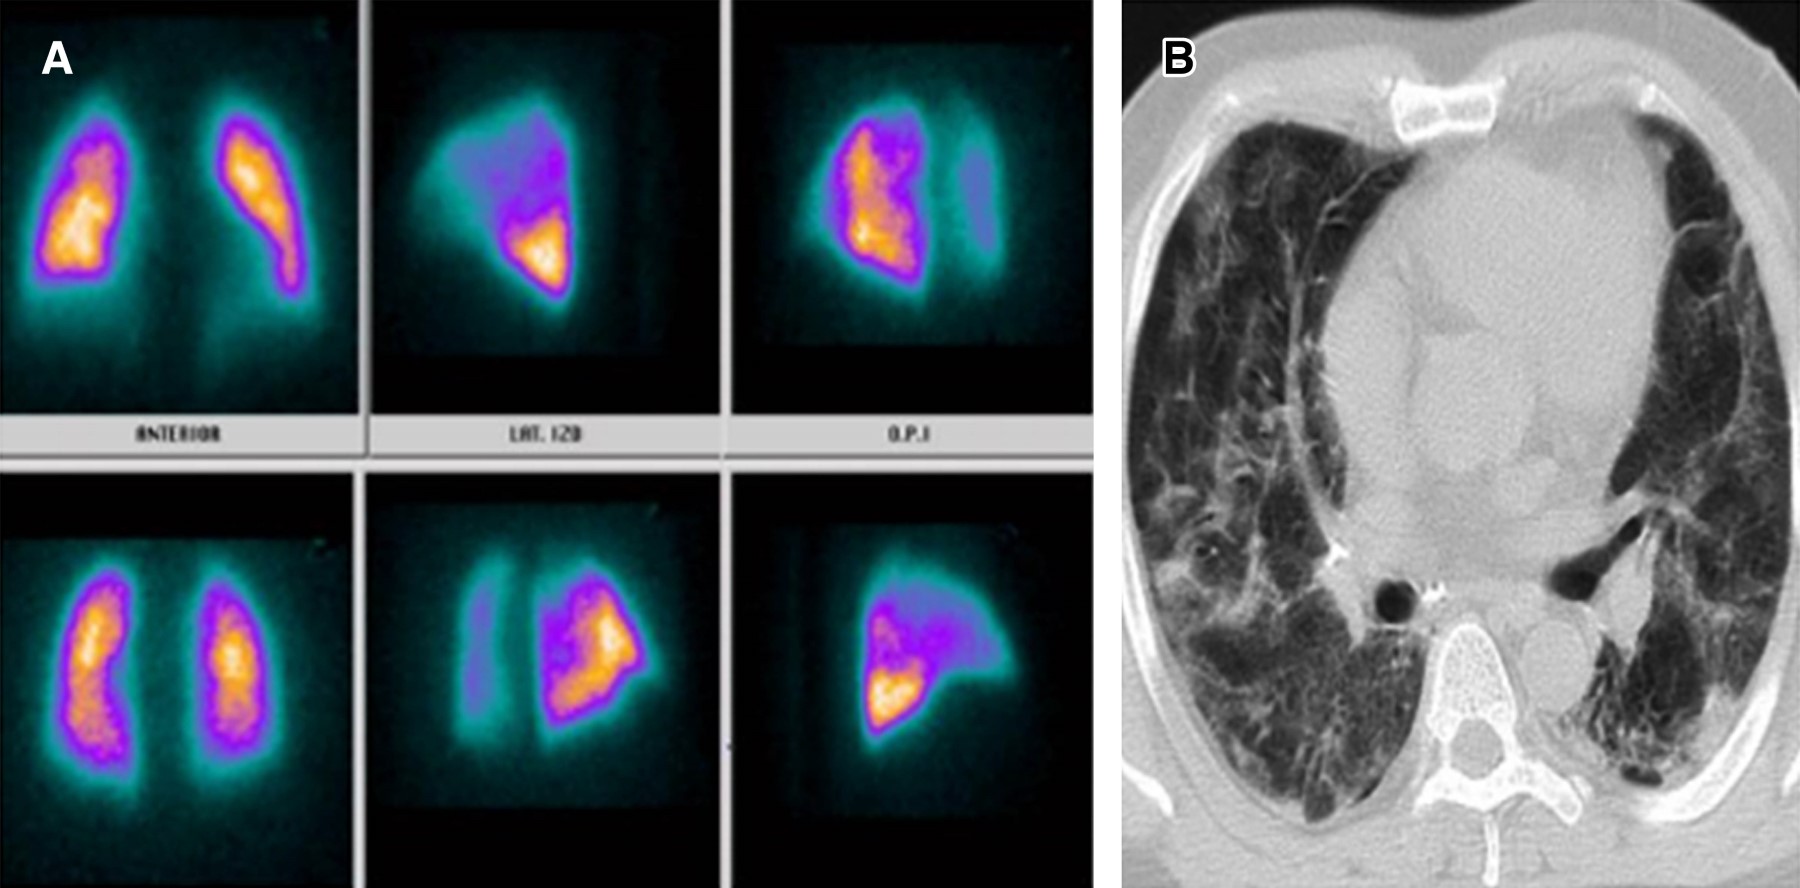

La infección por nuevo coronavirus es una entidad clínica altamente letal que trae consigo serias disfunciones celulares en primera línea de defensa, lo cual genera potentes mecanismos de hipercoagulabilidad mediados por reclutamiento de células inflamatorias.1 Uno de ellos direccionado por la disfunción del polimorfonuclear a partir del receptor 2 de enzima convertidora de angiotensina generado por la interacción de la fenilalanina ubicada en la porción 486 de la proteína de espiga del coronavirus, constituyéndose como el efecto más quimiotáctico existente, incluso superior al de la interleucina 8 (IL-8).2 A partir de esta situación, el reclutamiento del neutrófilo trae consigo la formación de una fina red inflamatoria inductora de integrinas denominadas NET (Neutrophil Extracellular Traps), produciendo activación de la vía intrínseca de la coagulación a partir del factor XII de Hageman. Adicionalmente, la muerte programada de dichas células, mediante la inducción de apoptosis, ocasiona liberación de histonas y restos de ADN, lo que precipita la formación de trombina.3,4 Por otro lado, la infección por nuevo coronavirus altera la respuesta del huésped al inóculo mediante modificación de los micro-ARN linfocitarios, lo que ocasiona disfunción del fagosoma natural en estadios de inmunocompetencia exacerbada o inmunosupresión manifiesta que a la postre desencadena estrés oxidativo, liberando grupos de proteínas de elevada movilidad (High Mobility Protein Box 1 [HMGB1]) y generando inflamación, coagulación y apoptosis.5 Pero, sin duda alguna, la linfopenia inducida por el coronavirus tipo 2 se constituye como el determinante más letal de trombosis mediante activación de la vía extrínseca e intrínseca de la coagulación, de la mano de un influjo descomunal de trombina. Se han identificado tres mecanismos de muerte celular programada en el linfocito de pacientes con la enfermedad por coronavirus del 2019 (COVID-19); uno de ellos es por activación del factor de transcripción nuclear y factor nuclear kappa beta, otra es por la activación del mitógeno p37 de la proteincinasa y la más deletérea mediante autofagocitosis determinante de un potente estado protrombótico.6 Con base en el conocimiento de los escenarios disfuncionales hematológicos durante la infección por nuevo coronavirus, se hace perentoria la predicción de enfermedad pulmonar tromboembólica, existiendo la duda razonable entre la prevención y la terapia antitrombótica, motivo por el cual la presencia de marcadores de actividad de fibrinolítica debe ser validada en tiempo presente y real. Teniendo en cuenta la mejor sensibilidad y especificidad disponible, las diferentes técnicas de enzimas líticas de inmunoensayo, hemaglutinación y látex deben someterse a consideración durante la estratificación diagnóstica.7,8 Una vez discriminados los pacientes con SARS-CoV-2 con pretest clínico medio para enfermedad pulmonar tromboembólica con reporte de dímero D por técnica de látex positivo y cuyos resultados de angio-TAC descartaron tromboembolia pulmonar (TEP); se les documentó, desde el punto de vista imagenológico, los defectos segmentarios de distribución vascular con morfología triangular de base externa y vértice interno por medicina nuclear, los cuales se correlacionaron muy de cerca con hallazgos en escanografías simples de tórax con atelectasias, efusión pleural y condensaciones, así mismo la presencia de alta probabilidad para TEP se validó por criterios de PISAPED (Figura 1, 2, 3, 4, 5, 6 y 7).9

Figura 1